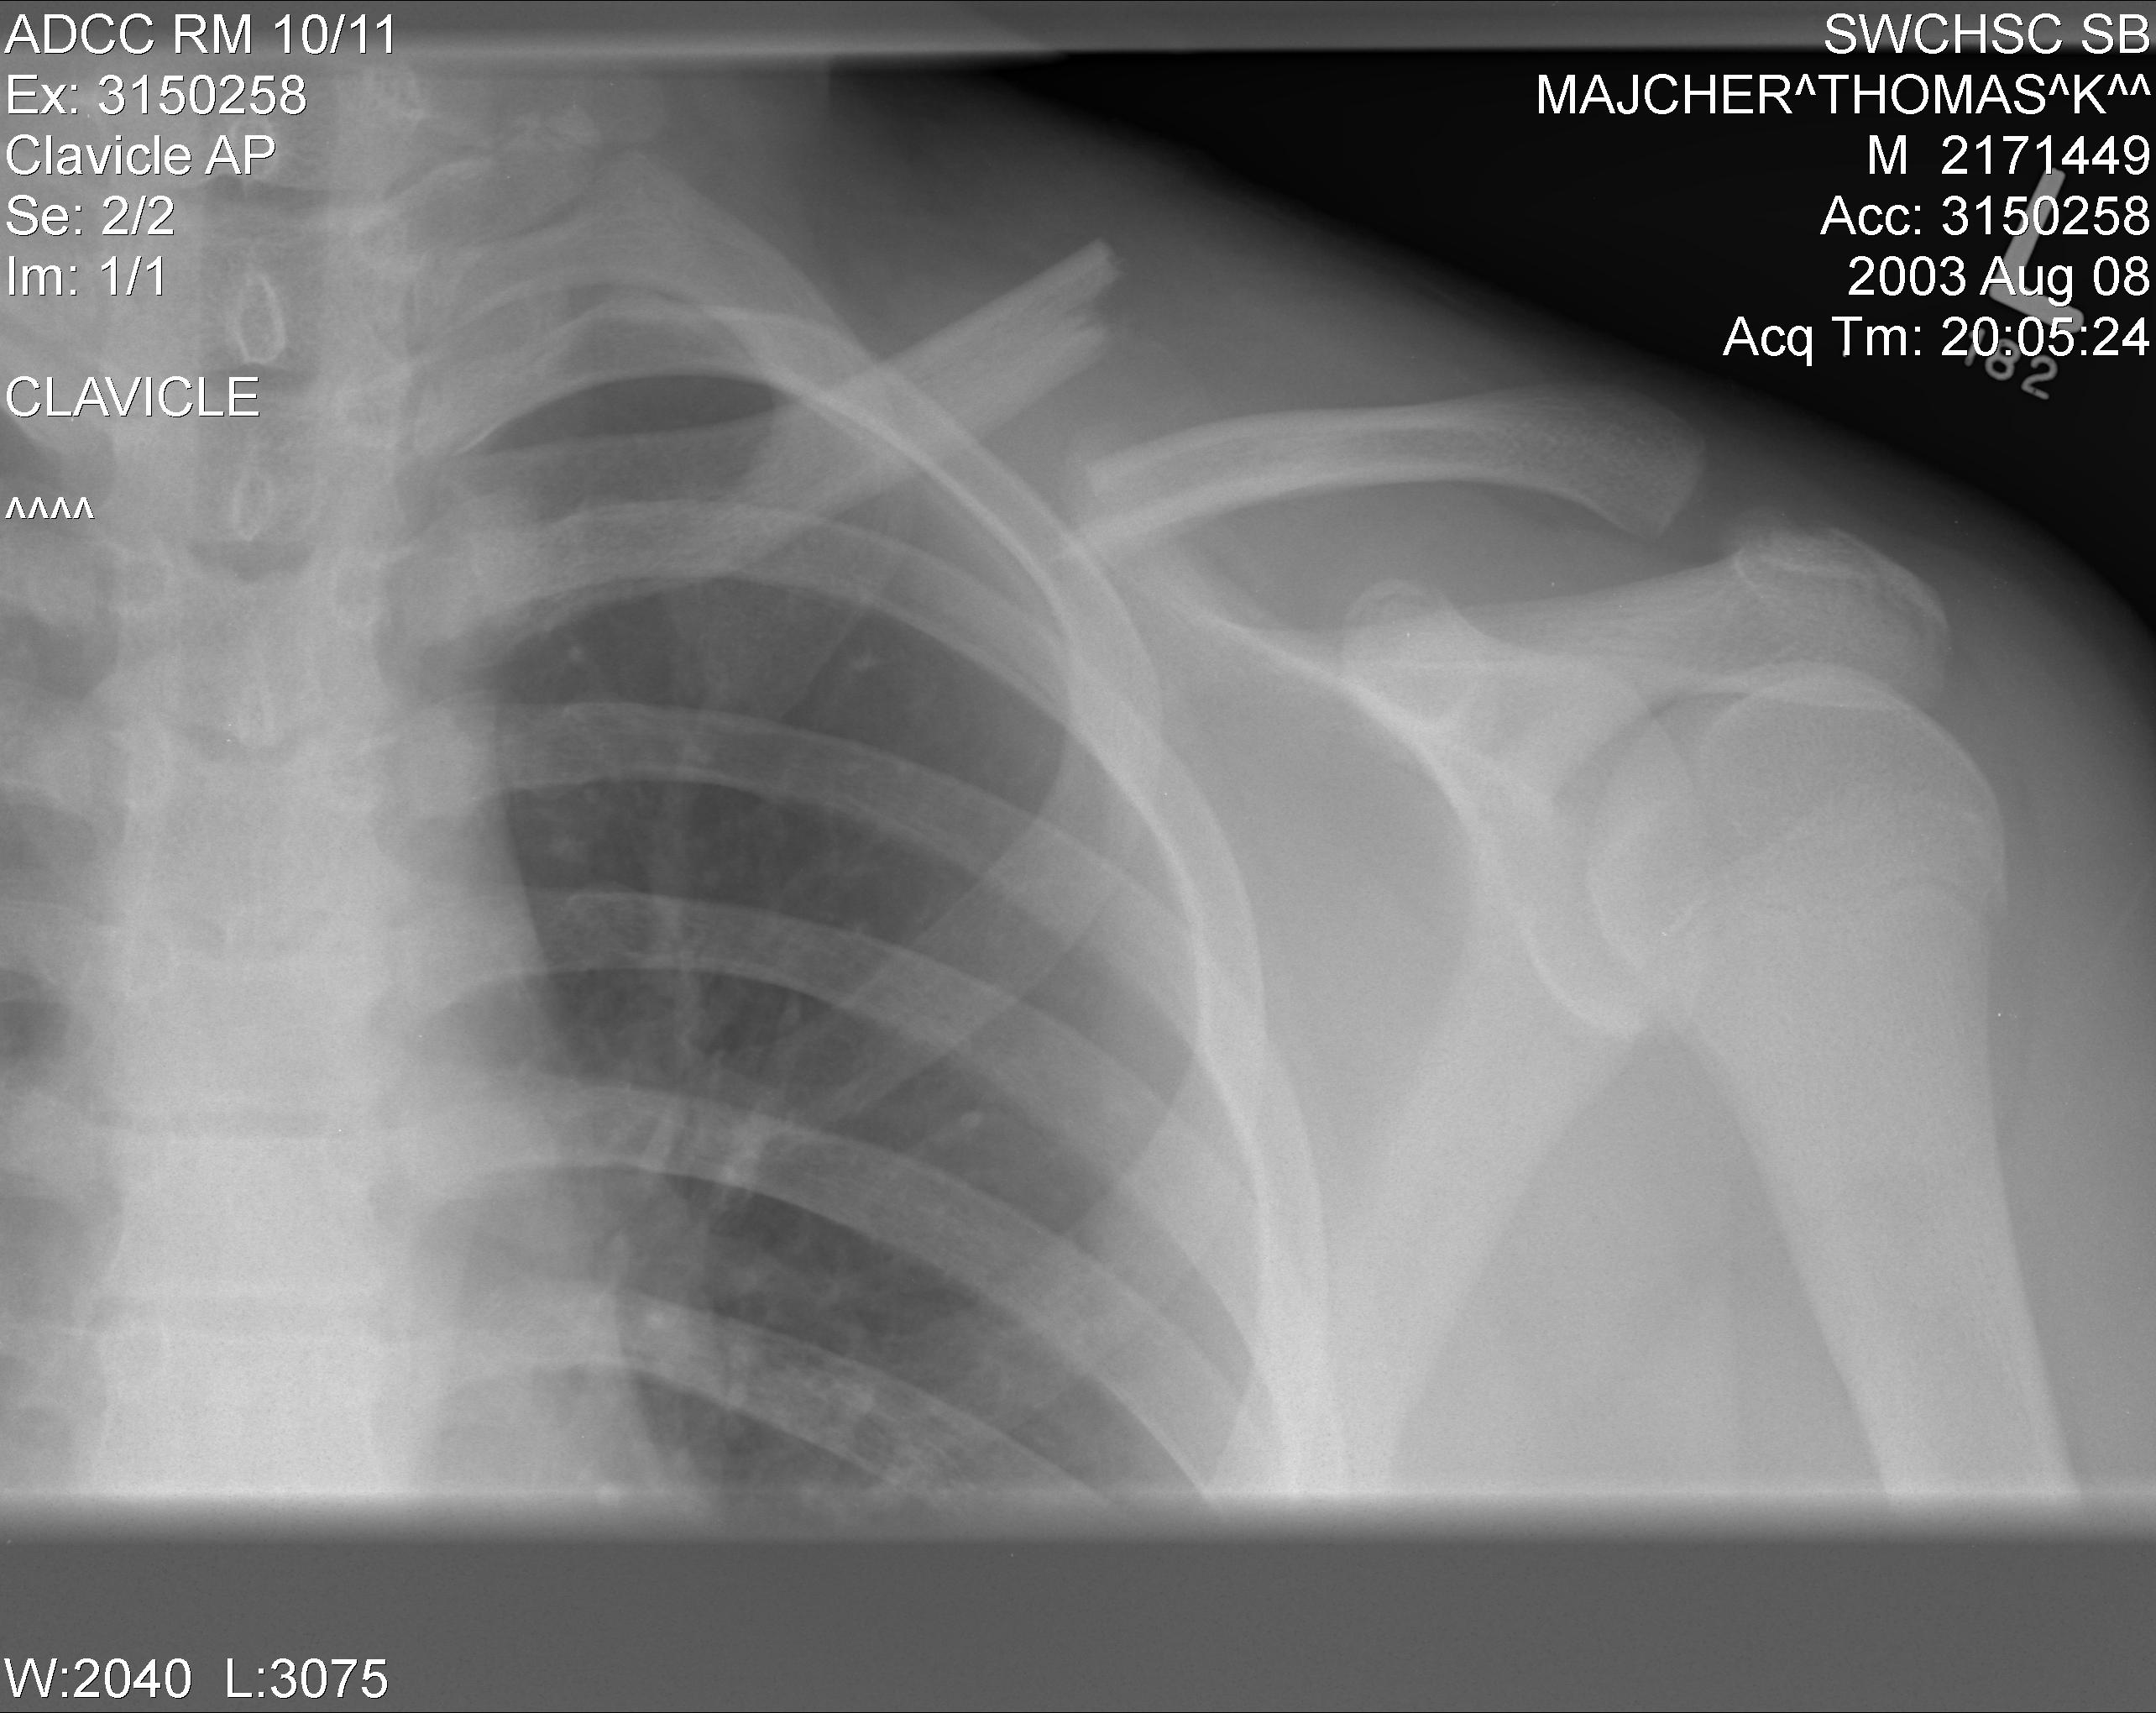

релом Ключицы У Ребенка Фото

Перелом Ключицы У Ребенка Фото 111 фотографий